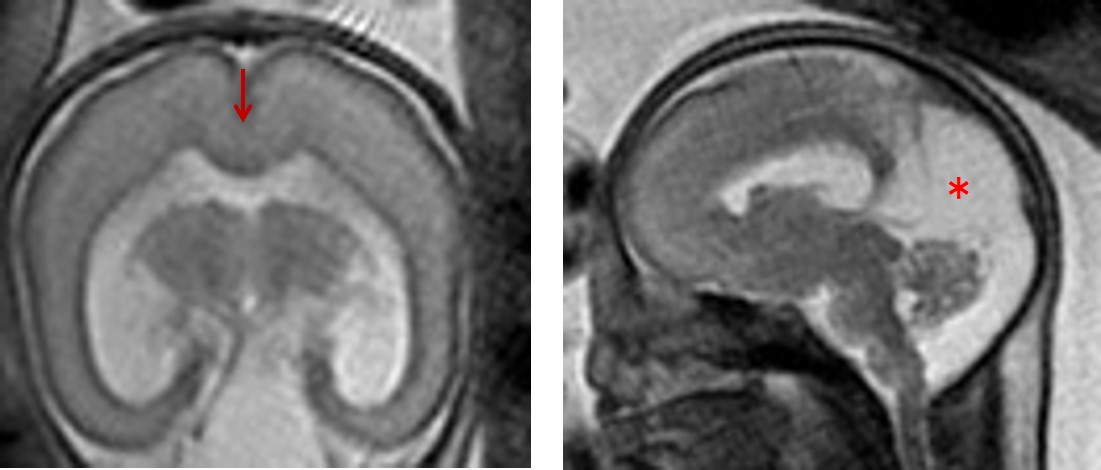

図2:完全脳梁欠損症のMRI

左;矢状断;脳梁の完全欠損を認める。

右;冠状断;側脳室前角は三日月状を呈する(↓)。第三脳室は半球間裂に向かって挙上する(*)。

図3:半葉型全前脳胞症の胎児MRI

大脳の前頭部正中で皮質の連続性が確認できる(↓)。Dorsal cystを認める(*)。